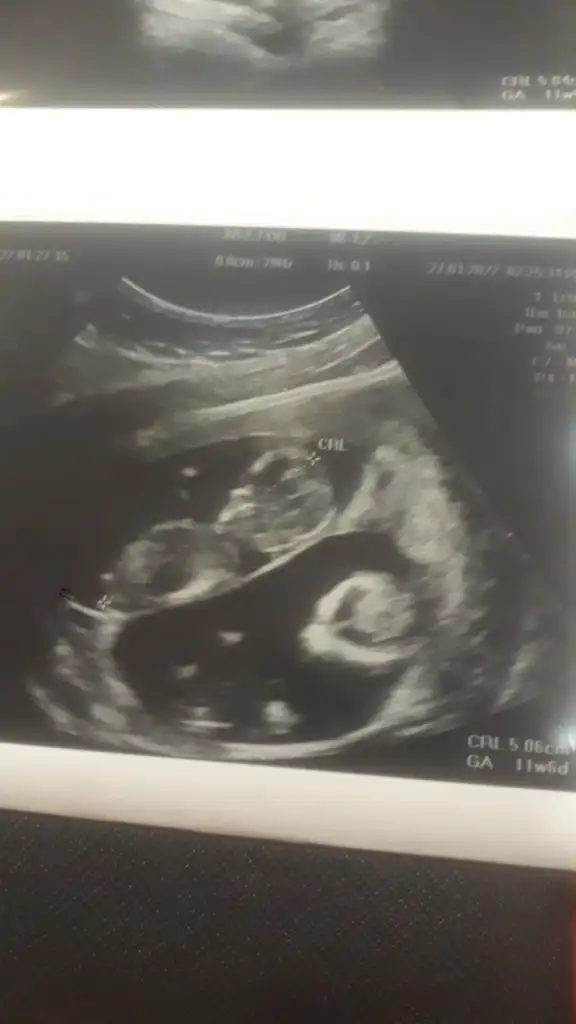

Şükür kuzum harika haber benimde hep bı hafta önde çıktı doktor hiç önemi yok dedi o fetal dna yi hatta aminosentezi bile ikili de anlattı bilgi vermek zorunda lar sanırım herkese kağıtta öle yaziodu .şükür darısı başımıza canim ya uyumasi iyi daha rahat bakmıştır yerinde durmuolar sonraKuzum anca müsait olabildim.

SAT’a göre 21+3 olmasına rağmen, USG ölçümüne göre 22+3 göründü. Dondurulmuş embriyo transferinde beklediğimiz bir şey bu, problem değil dedi.

Oyy maşallah maşallah kuzularımaGünaydın canım iyiyim çok şükür sen nasılsın nasıl gidiyor yok kuzum dr cuma günü kesin soylerim dedi cinsiyeti ama bence gördü biseyler o yüzden o kadar emin cums günü söylerim dedi bende iki kız hissediyordum ultrason görüntüsüne kadar biri icin herkes erkek oyunu kullandı diğeri kız olabilir dedi herkesbak görüntüleri atıyorum